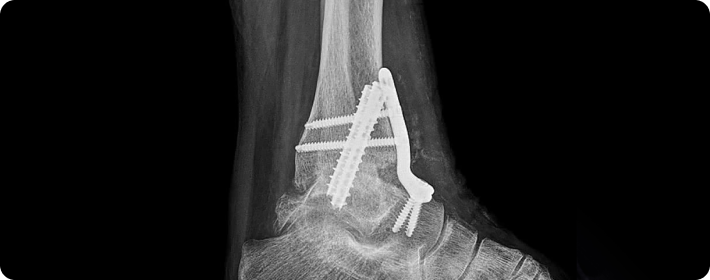

골절고정술

부러진 뼈를 정확한 위치에 맞춘 뒤, 금속판, 나사, 핀 봉 등을 이용해 단단히 고정하여 뼈가 바르게 치유되도록 돕는 수술입니다. 뼈의 정렬을 유지하고 회복을 촉진하는 데 중요한 치료입니다.

• 관절 안정성 회복

• 장기적인 효과

• 재발 예방